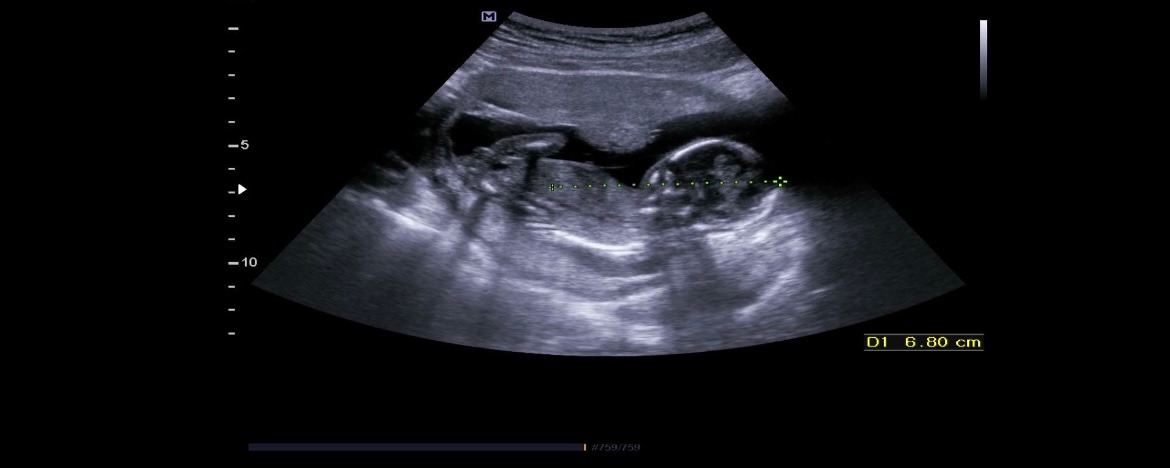

KakaoTalk_20230629_161811899.jpg 6.8cm였던 우리 아가의 초음파 모습